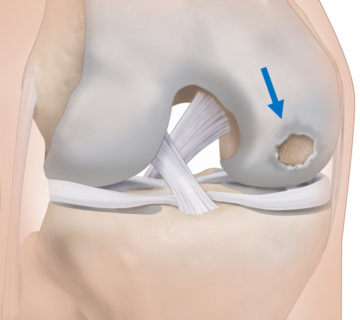

Otros motivos que pueden provocar la necesidad de colocar una prótesis es una fractura en un paciente muy mayor, una lesión crónica de los ligamentos de la rodilla con daño articular o una osteonecrosis de la rodilla con afectación del cartílago articular.

Pinche aquí para saber más sobre la patología del cartílago articular de la rodilla